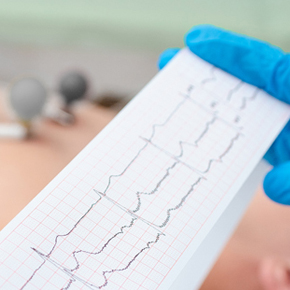

Tecnología de Punta

Equipos de última generación que agilizan nuestro servicio, brindando beneficios directos a todos nuestros pacientes.

- Monitor de Signos Vitales MediBlu®

- Colposcopio Eva Colpo 3 Plus

- Sistema de Ultrasonido Digital P3Plus